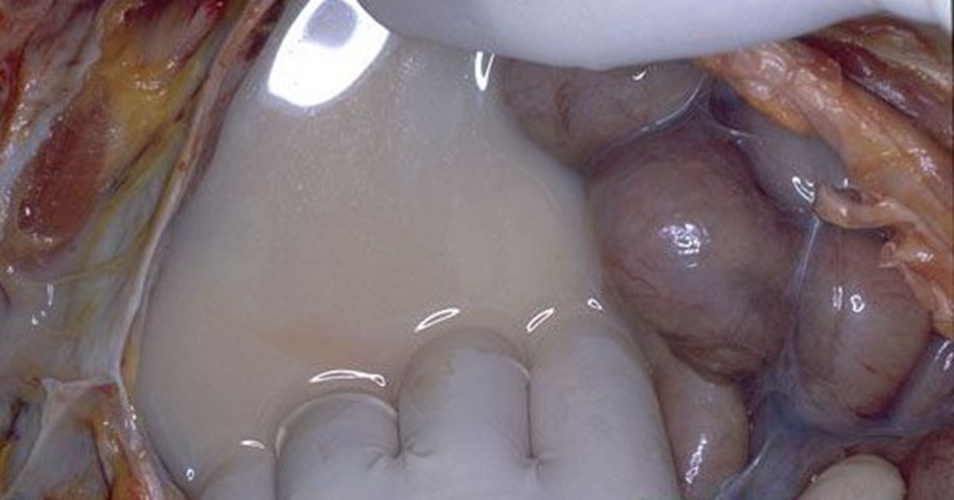

腹水圖片

有肚子腹水

有腹水患者